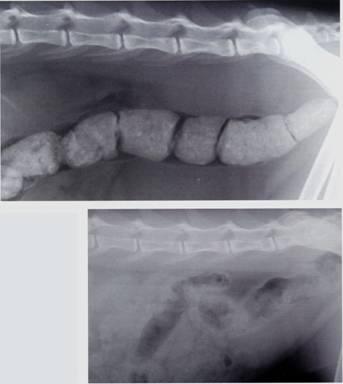

No he podido encontrar una sencilla explicación de, por qué mi gata tenía dos círculos sanguinolentos en las dos patas traseras. El veterinario me dijo: probables tumores. Cada vez más sumida, sin dientes (alimento húmedo) apenas comía y perdía pelo en abundancia. A pesar de mi educación, palabras difíciles de comprender. En imagen lo que vomitaba.